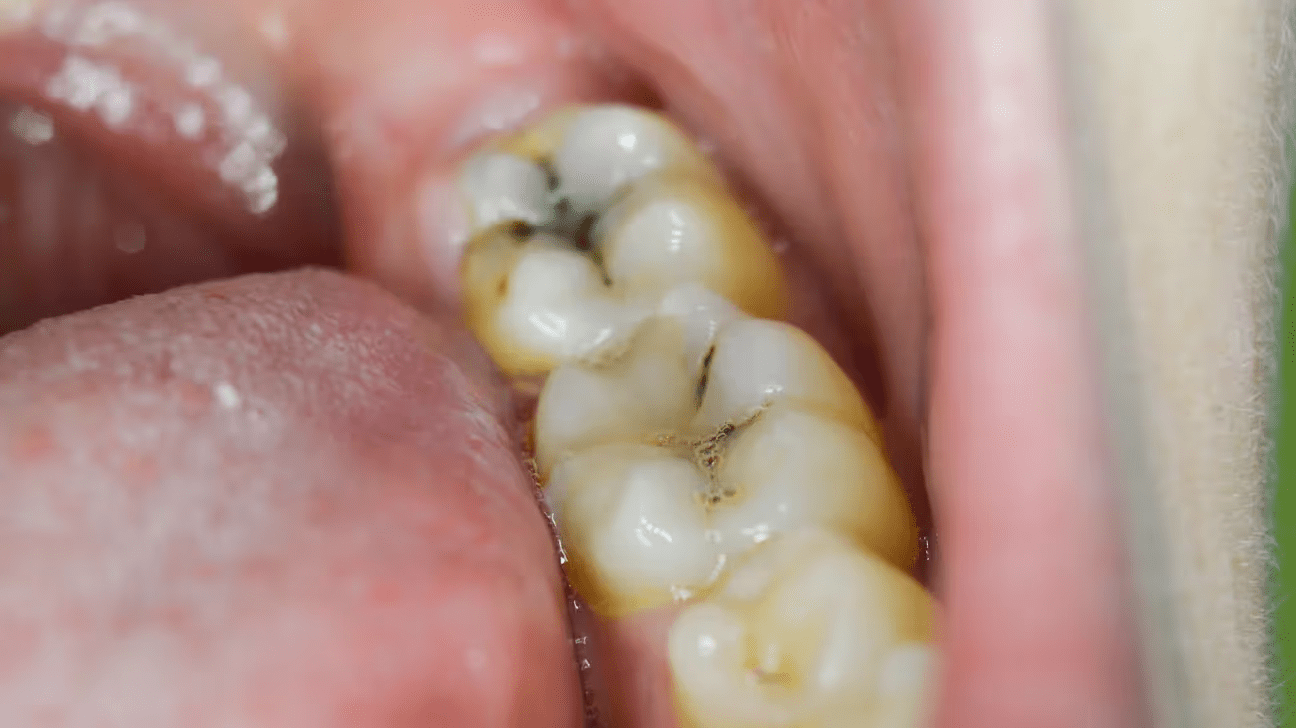

Cavities form when bacteria feast on sugars, producing acids that erode enamel. Sugary drinks, snacks, or even stress-induced grinding can speed this up. You might think brushing twice a day is enough, but many miss a key step. What’s the one thing your dental routine might be overlooking? Let’s explore a remedy that could make all the difference.

1. Fights Bacteria Like a Pro

Meet Sarah, a 47-year-old teacher who dreaded her dental checkups. Her mornings started with sensitivity that made her skip her favorite citrus fruits. Then she tried oil pulling. Swishing coconut oil for 10 minutes daily reduced her mouth’s bacteria, easing her discomfort. Studies, like one from the Journal of Traditional and Complementary Medicine, show coconut oil’s lauric acid can reduce harmful bacteria by up to 50%. Less bacteria, fewer cavities. But how does it feel to reclaim your smile?

3. Strengthens Your Enamel’s Defense

Picture biting into a crisp salad without flinching. Coconut oil’s fatty acids may create a protective barrier on enamel, slowing acid damage. A 2019 study found oil pulling reduced plaque buildup in 80% of participants after two weeks. You might be thinking, “Is this too good to be true?” It’s not a cure, but it supports your brushing routine. What else can this remedy do for your daily comfort?